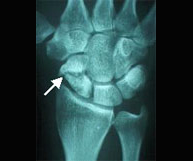

Dentro de la región anatómica de la muñeca se encuentran los huesos del carpo. El hueso escafoides es el que se fractura con más frecuencia tras caídas sobrela mano en extensión. Es por ello una lesión característica en deportes como motociclismo, ciclismo y patín donde se pueden sufrir traumatismos a gran velocidad. El dolor se localiza siguiendo el eje del pulgar pero a nivel de la muñeca y el dolor a la palpación en esta zona (tabaquera anatómica) es extremo. Las fracturas desplazadas se suelen estabilizar quirúrgicamente sin cicatriz,a través de la introducción percutánea de un tornillo intraóseo que permite el inicio de la movilización de la articulación inmediatamente.